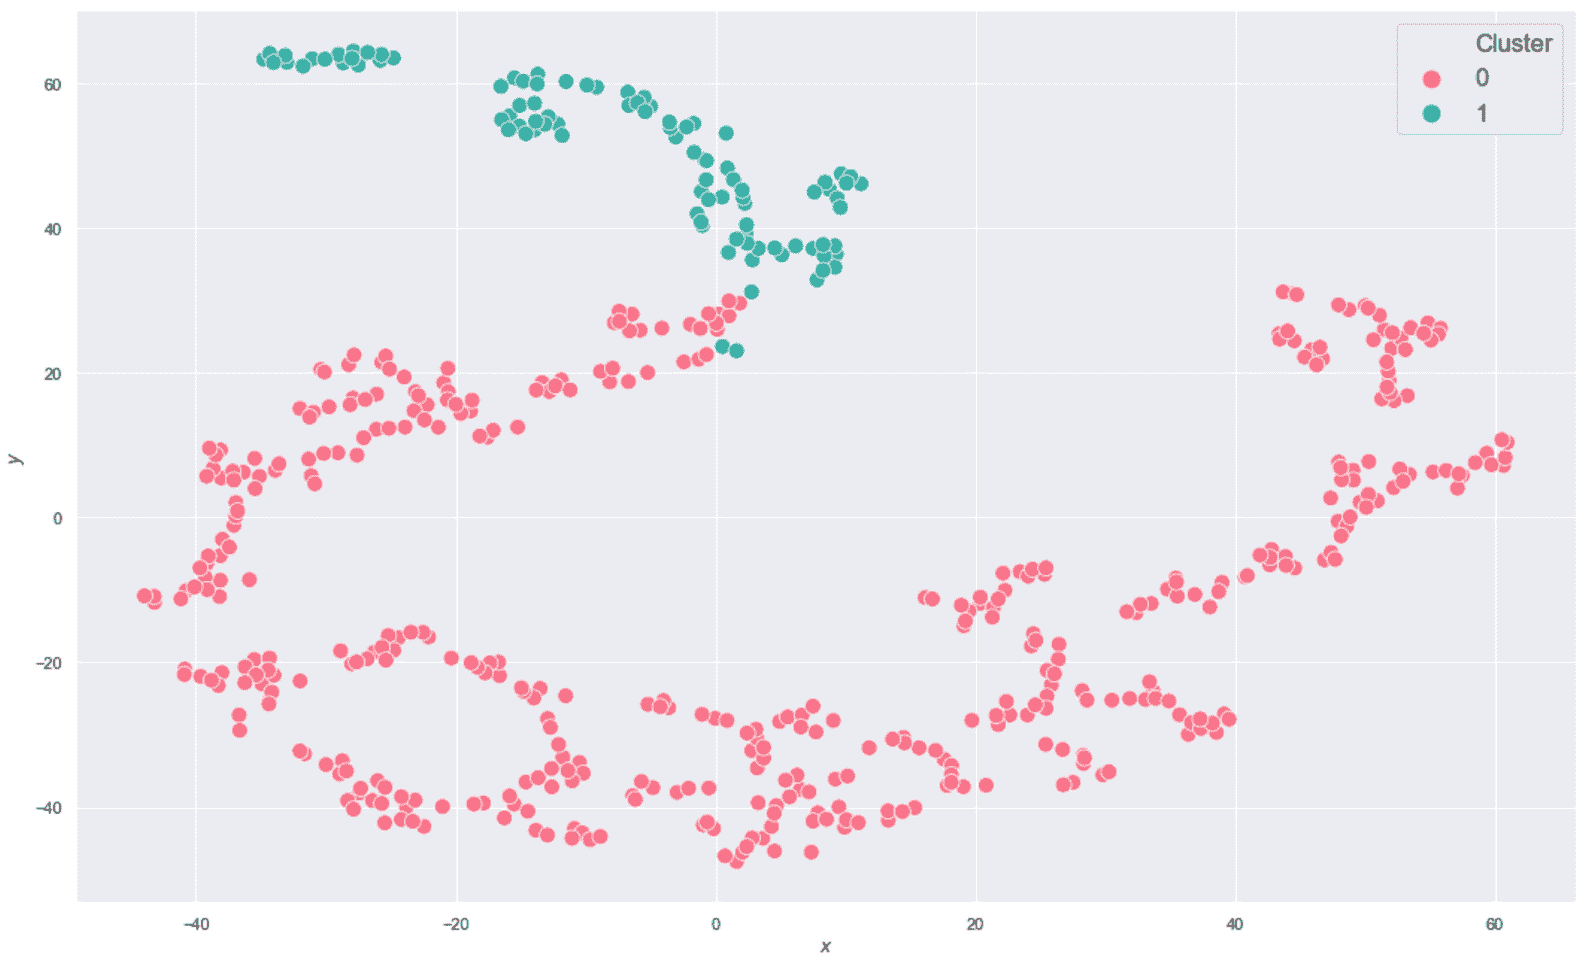

该图是高度非线性的(别忘了这是从ℜ^30到ℜ^2的投影),恶性样本中的一半在半平面y < 0中。 不幸的是,在该区域中也有适度的良性样本,因此我们不期望使用K = 2进行完美分离(在这种情况下,很难理解真实的几何形状,但是 t- SNE 保证二维分布的 Kullback-Leibler 散度与原始高维散度最小。 现在,我们以K = 2进行初始聚类。 我们将使用n_clusters=2和max_iter=1000创建KMeans scikit-learn 类的实例(random_state始终设置为等于1000)。

生成的绘图显示在以下屏幕截图中:

乳腺癌威斯康星州数据集的 K 均值聚类(K = 2)

毫不奇怪,该结果对于y < -20相当准确,但该算法无法同时包含边界点(y≈0)进入主要恶性集群。 这主要是由于原始集合的非凸性,并且使用 K 均值很难解决问题。 此外,在投影中,大多数y ≈ 0的恶性样本与良性样本混合在一起,因此,使用基于接近度的其他方法的错误概率也很高。 正确分离这些样本的唯一机会来自原始分布。 实际上,如果可以通过ℜ^30中的不相交球捕获属于同一类别的点,则 K 均值也可以成功。 不幸的是,在这种情况下,混合集看起来非常具有内聚性,因此我们不能指望不进行转换就可以提高性能。 但是,出于我们的目的,此结果使我们可以应用主要评估指标,然后从K > 2移到更大的值。 我们将使用K > 2分析一些聚类,并将它们的结构与配对图进行比较。

生成的绘图显示在以下屏幕截图中:

乳腺癌威斯康星州数据集的 K 均值聚类(K = 8)结果